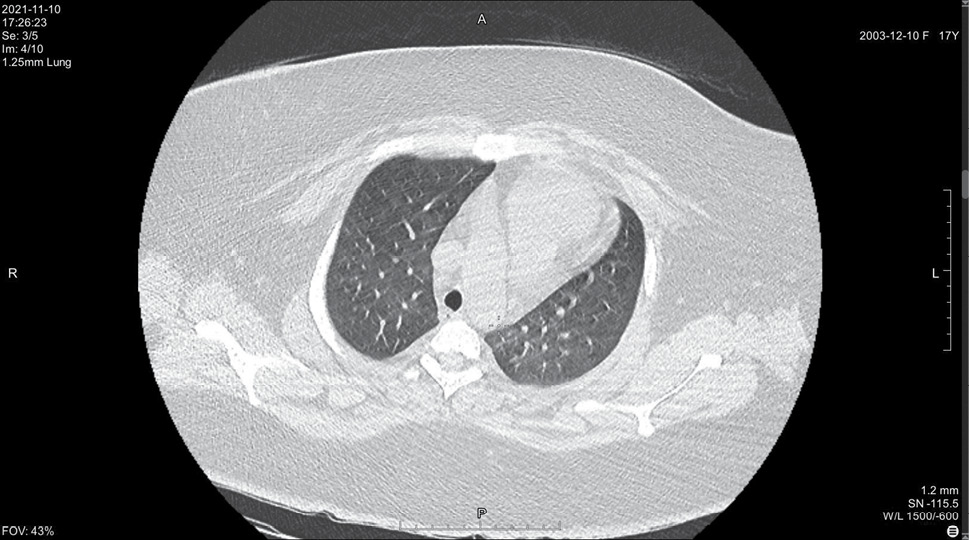

На 14 день болезни (10.11, 7 день госпитализации) была выполнена спиральная компьютерная томография грудной клетки, где выявлены признаки двусторонней интерстициальной полисегментарной пневмонии (рис. 1–8). Форма грудной клетки описана как обычная. Легочные поля расправлены. На томограммах бронхиальное дерево визуализировано до субсегментов: сами бронхи не деформированы, их просвет в пределах нормы, устья свободны, проходимость сохранена на всем протяжении. Во всех сегментах с обоих сторон определялись полиморфные, сливные участки уплотнения легочной ткани по типу матового стекла с участками консолидации. На этом фоне были видны просветы бронхов. Определялись фиброзные тяжи в проекции апикальной плевры обоих легких. Контуры диафрагмы четкие, синусы свободные, свободная жидкость в плевральной полости отсутствовала. Трахея обычной формы и размеров, карина острая. Сосудистые структуры верхнего средостения с четкими контурами и нормального диаметра, стенки сосудов без кальцинатов. Медиастинальные лимфоузлы и лимфоузлы корней обоих легких (без контрастного усиления) визуализированы единично, не увеличены. Сердце расположено обычно, размеры в пределах нормы. Выявлены умеренные дегенеративно-дистрофические изменения грудного отдела позвоночника. Мягкие ткани грудной клетки без особенностей. По заключению врача-рентгенолога, объем пораженной легочной паренхимы достигал 95%. Наиболее вероятно, что патологический процесс у пациентки имел вирусную природу.

Рисунок 3. Томограмма легких на уровне ThV

Рисунок 4. Томограмма легких на уровне ThVI